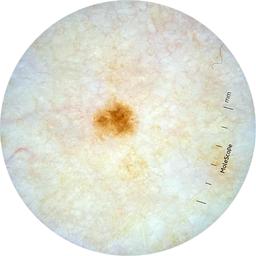

ISIC_9097190

Information

Dimensions

2049 x 2049

Attribute to

MEL-SELF Trial, https://www.sydney.edu.au/medicine-health/our-research/research-centres/melself-project.html

License

Clinical

Field Value

acquisition_day 181

age_approx 45

anatom_site_1 Trunk

anatom_site_2 Anterior trunk

anatom_site_general anterior torso

diagnosis_1 Benign

family_hx_mm False

fitzpatrick_skin_type I

image_manipulation instrument only

image_type dermoscopic

lesion_id IL_9115938

patient_id IP_3026018

personal_hx_mm True

sex female